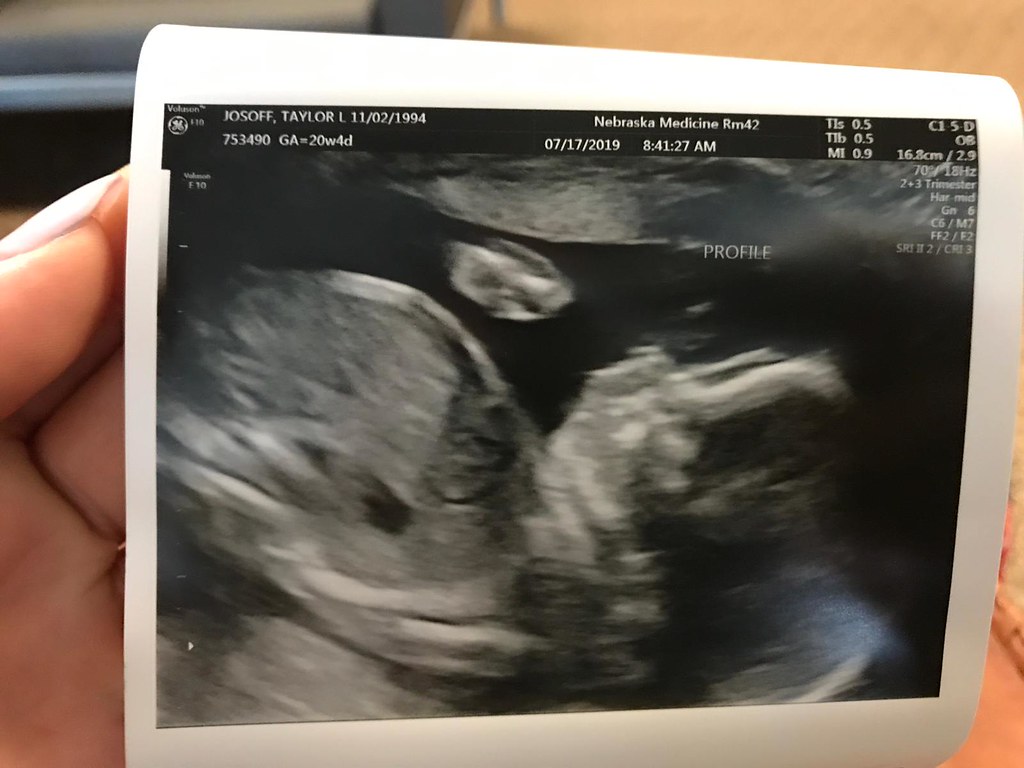

Grandbaby #4—can’t wait to meet this little dude or dudette in November!